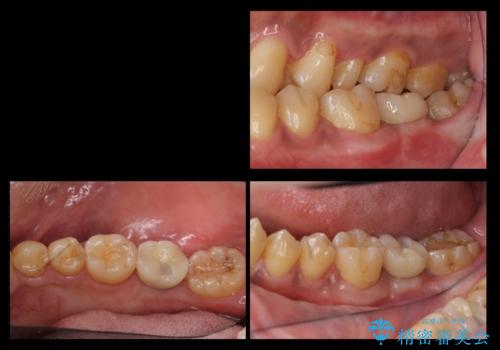

- 奥歯が割れたあと、他院で抜歯したところにインプラントを希望して来院。2回法で行いました。

奥歯を抜いたまま放置すると後方の歯が前に倒れこんでしまい、かみ合わせやその後の治療に支障がでます。早めに処置することをおすすめします。